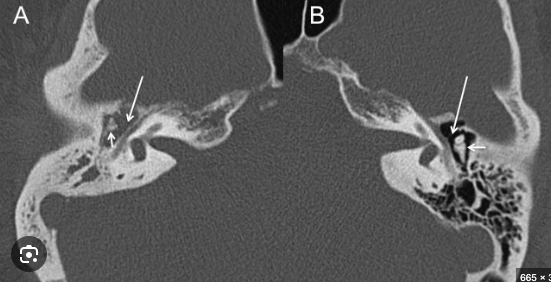

Mejor estudio de imagen para otitis media:

TC

Compara: no hay aire

Hallazgos de TC en otitis media:

• Masa bien definida en oídeo medio: densidad intermedia

• Erosiones osiculares

Asociado a mastoiditis